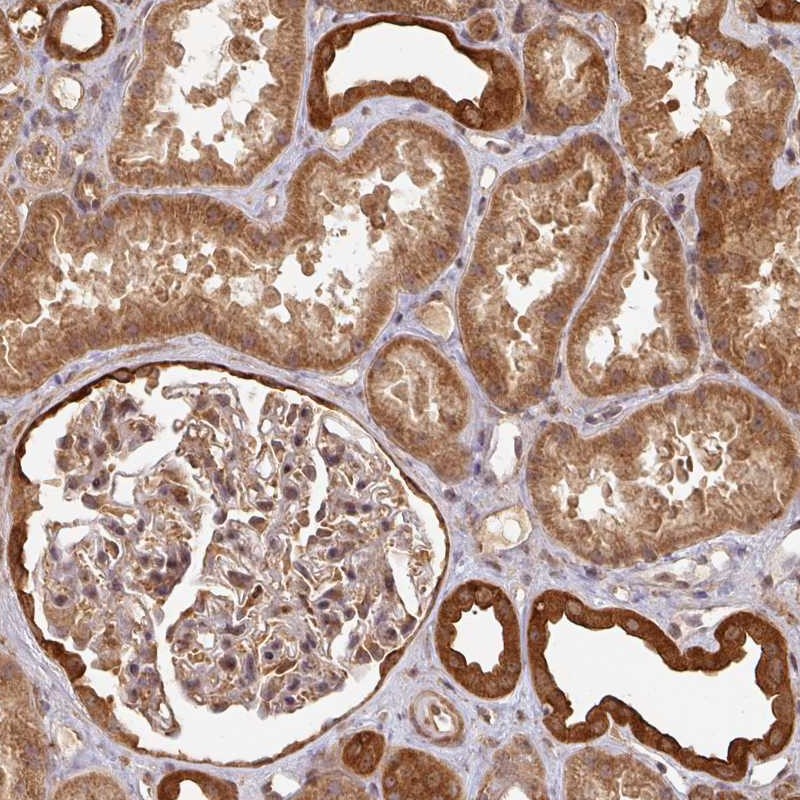

Immunohistochemical staining of human kidney shows distinct cytoplasmic positivity in cells in tubules.